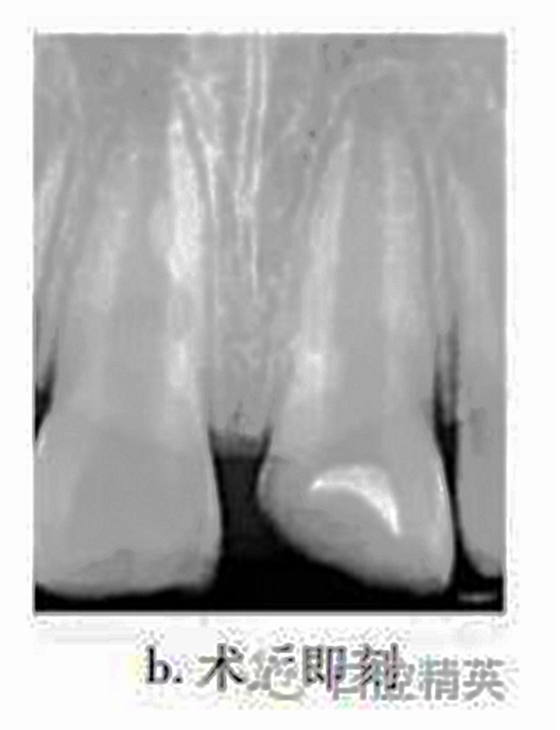

治療:局麻下調(diào)牙合,21揭髓頂,去除可能污染的冠部牙髓,達根管口處,呈整齊斷面,生理鹽水反復沖洗以去盡組織碎屑,并用蘸有少許生理鹽水的小棉球置于牙髓斷面壓迫止血,將MTA按操作說明要求和生理鹽水按3∶1比例調(diào)和均勻呈糊狀,直接覆蓋在牙髓斷面約1mm,玻璃離子水門汀暫封(圖b)。